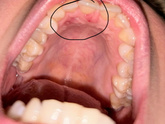

Точка у глаза

22 октября 2024 12:24

Всегда интересовалась что за точка как дырка возле глаза. Может у кого так же?) просто такое строение? У меня всю жизнь эта штука есть)